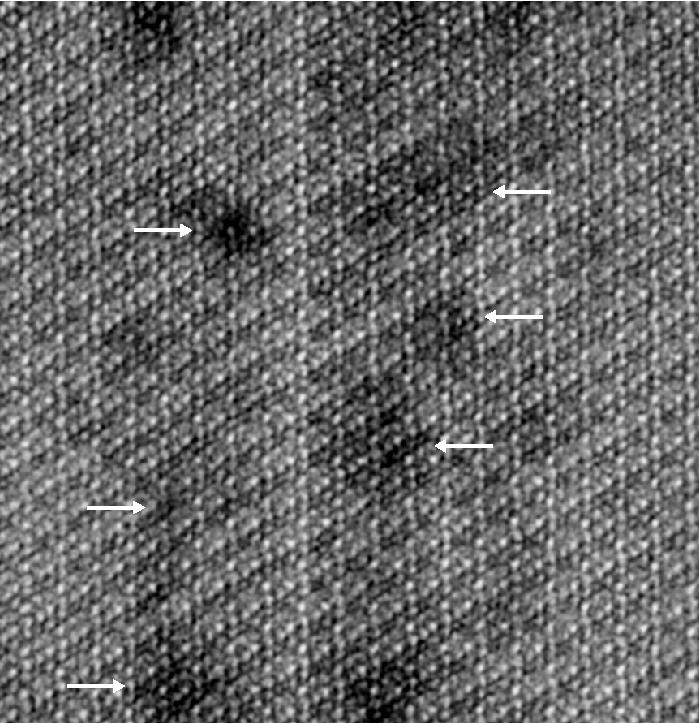

The results showed that the crystallites were made of a continuous uniform lattice of hydroxylapatite atoms. However, the lattice structure appeared to be sprinkled with dark distortions, especially at the innermost core of the crystallites.

A closer look at the core revealed that these defects were caused by the presence of minor elements that previous studies had hinted at. One such element was magnesium, which was highly concentrated in two distinct layers in the core. The central region was also rich in sodium, fluorine, and carbonate. Flanking the core was a "shell" with much lower concentrations of these elements.